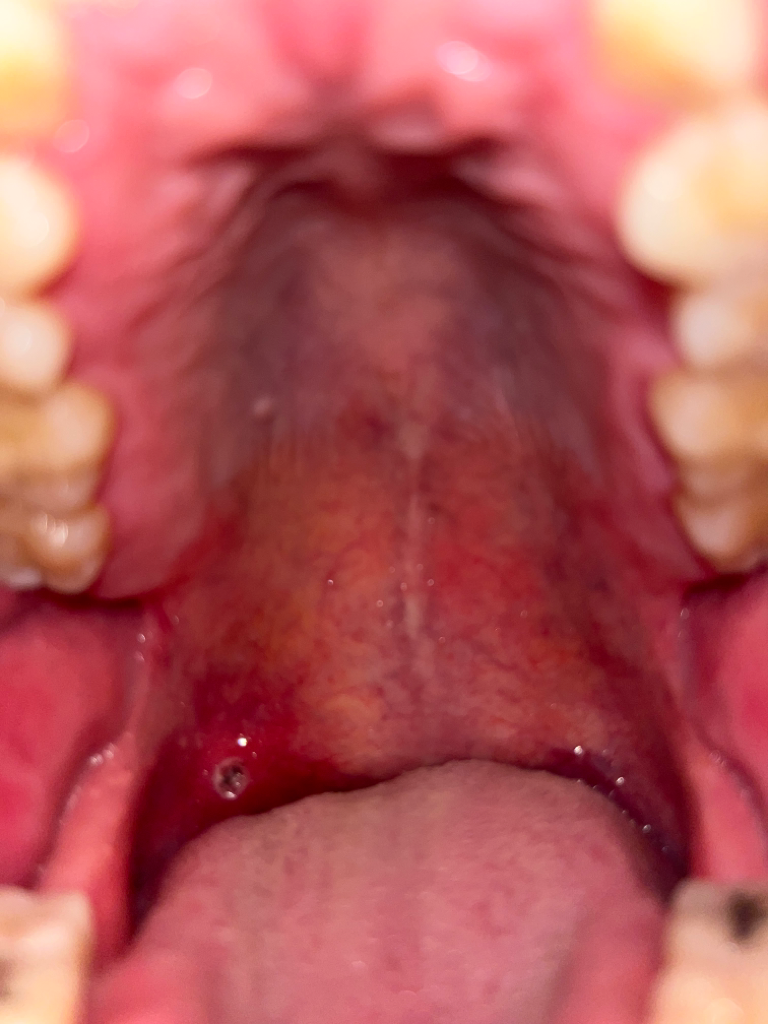

이거 구강암인가요? 구내염인가요?

어제 부터 입천장에 구내염의 흰색이 나다. 오늘 알보칠로 치료하였고, 저녁에 약을 바르기 위해 발랐더니 흰색 껍질이 벗겨지면서 현재 사진과 같이 흰색 + 검정반점이 안에 있는데요 ㅠㅠ

치료하고 난 후의 병변이라면 구내염입니다. 구내암일 가능성은 거의 없어요. 그냥 지켜보시면 됩니다.